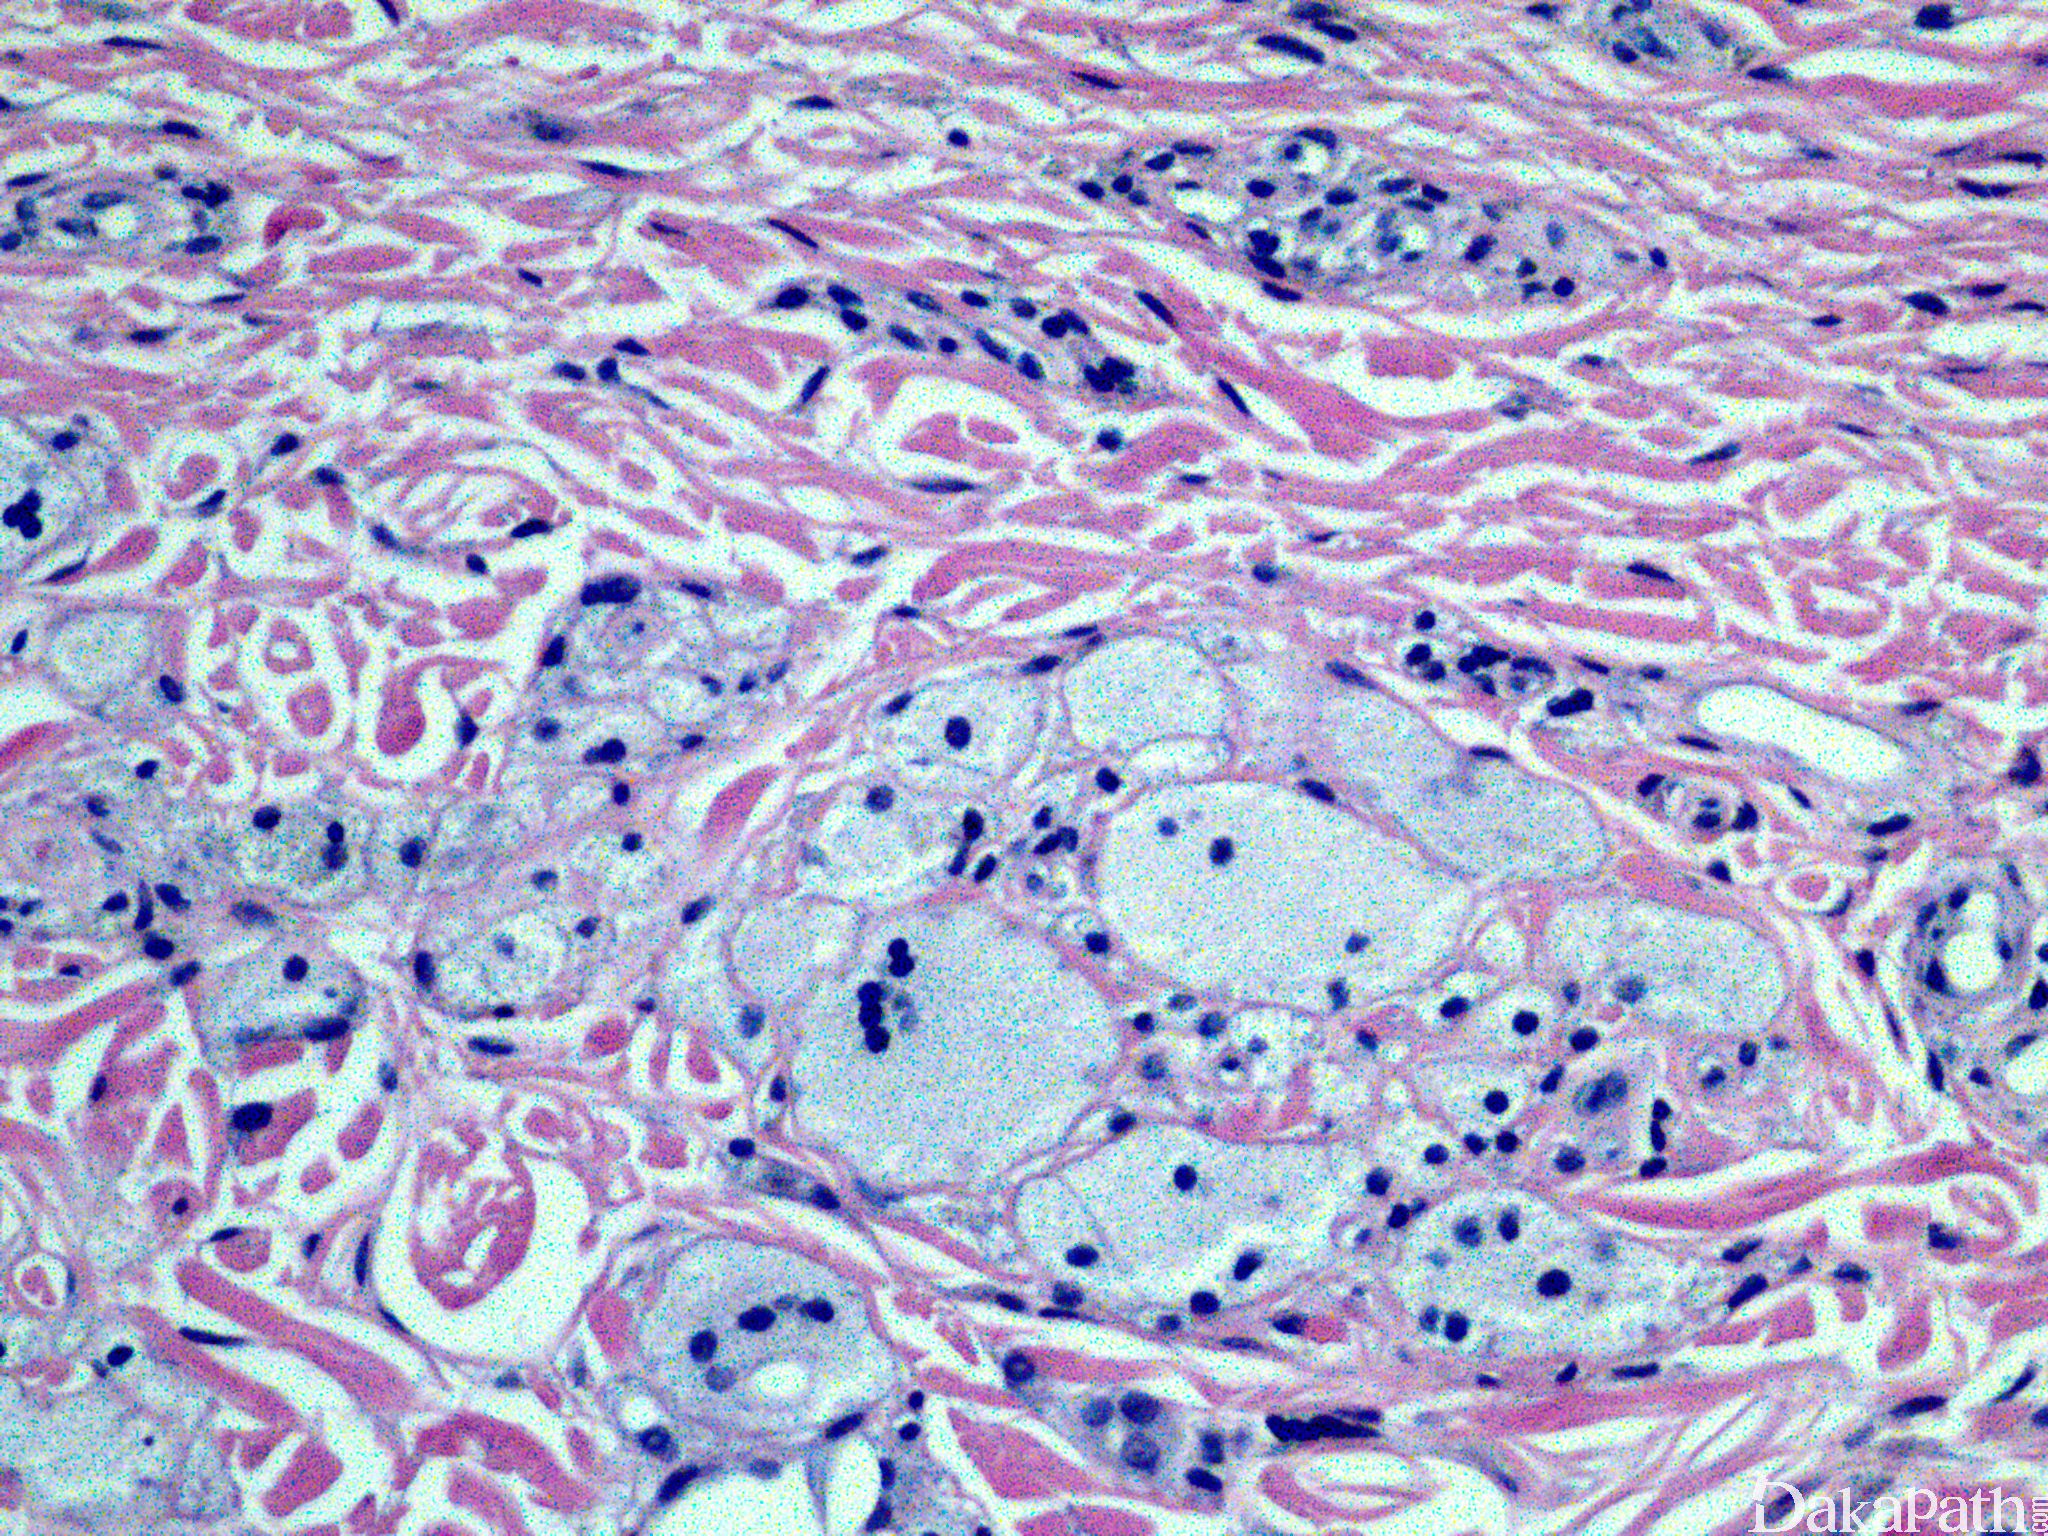

疣状黄瘤

坏死性黄色肉芽肿瘤